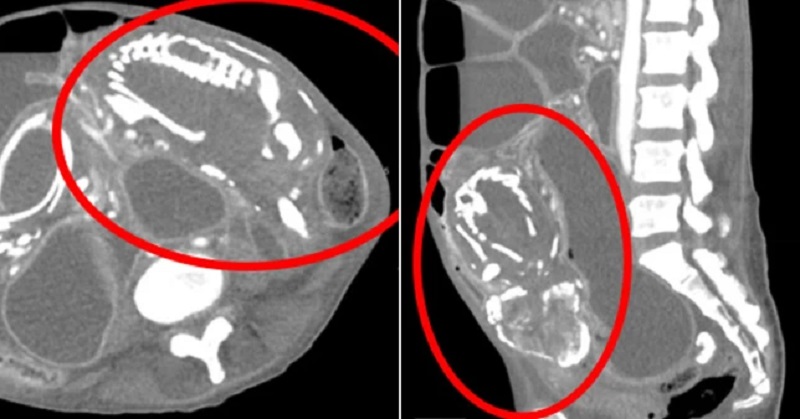

اسکنها نشان داد که او یک جنین کلسیفیه، که به آن «کودک سنگی» نیز میگویند، در داخل رودههایش داشت که باعث انسداد شدید روده و سوء تغذیه وی شده بود.جنین متولد نشده این زن در شکمش گیر کرده بود و مانع جذب مواد مغذی می شد.

این اتفاق زمانی میافتد که جنین در شکم رشد میکند و نه در رحم. پس از اینکه جنین می میرد، باعث کلسیفیه شدن و «سنگ یا آهکی شدن» آن میشود و اندامهای اصلی را فشرده میکند و جذب مواد مغذی مادر را محدود میکند.